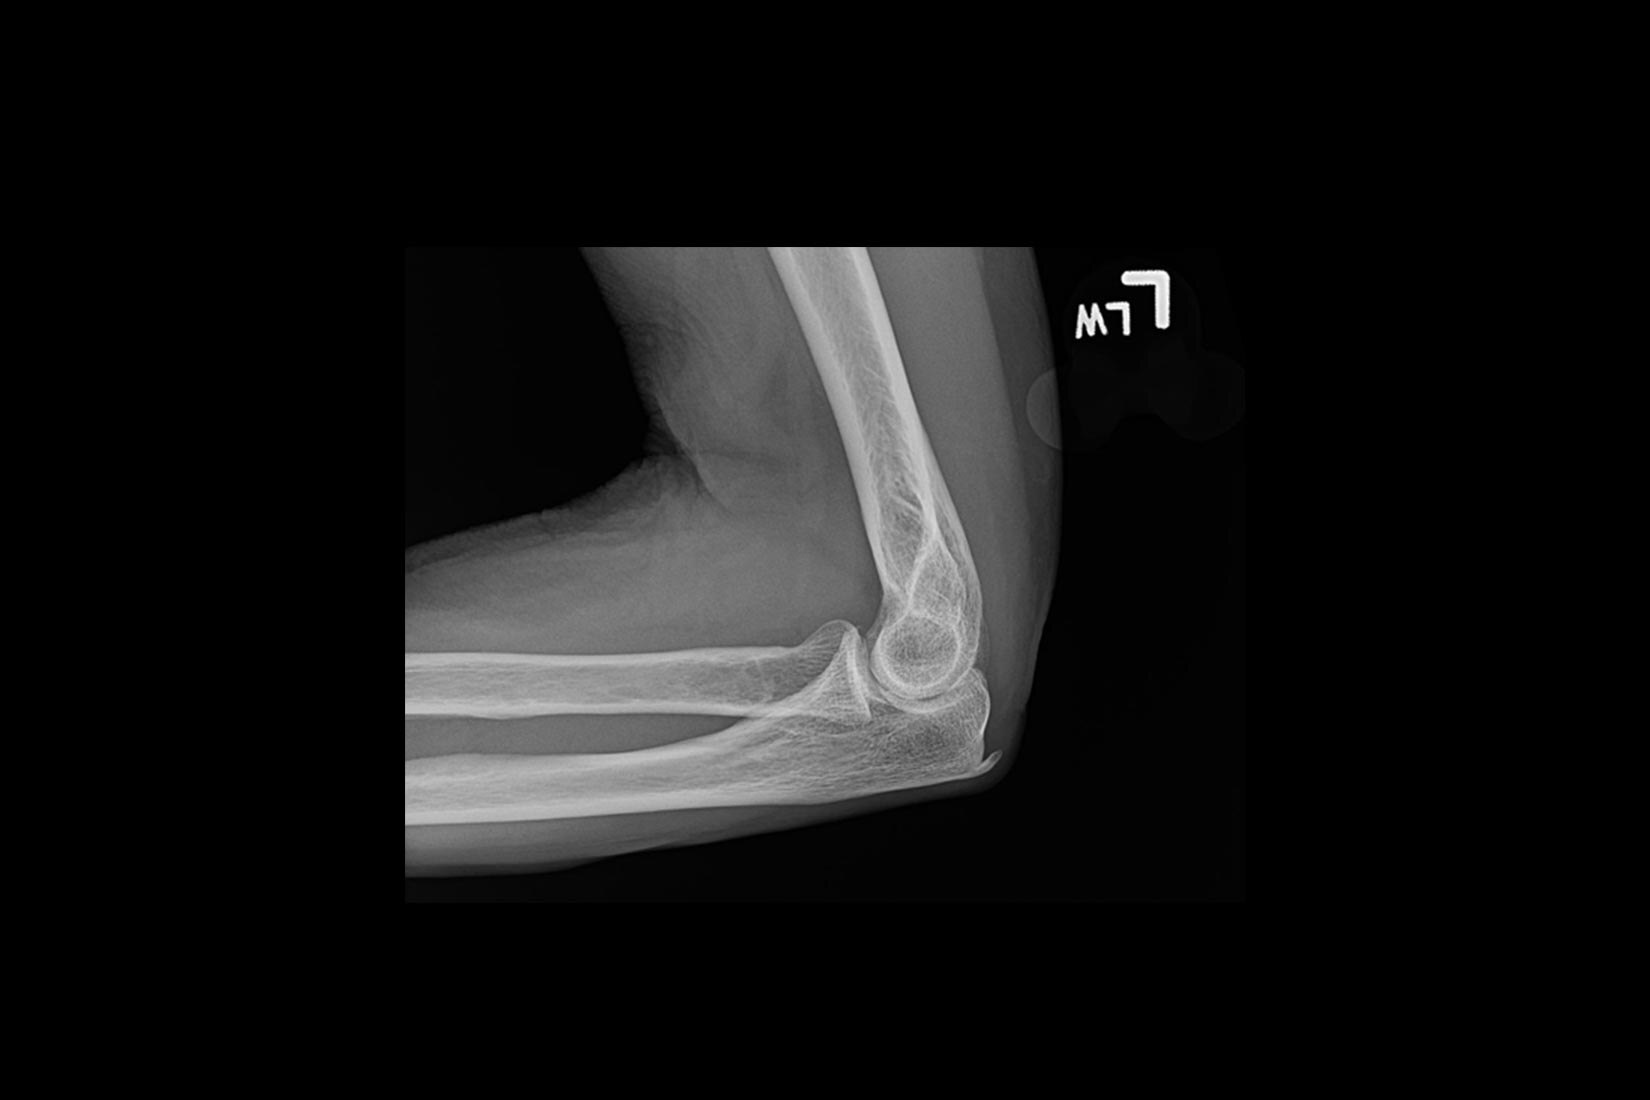

Transdutores Venue

Vivencie imagens claras em uma gama de pacientes, de adultos a pediátricos com os transdutores mais recentes para a família Venue.